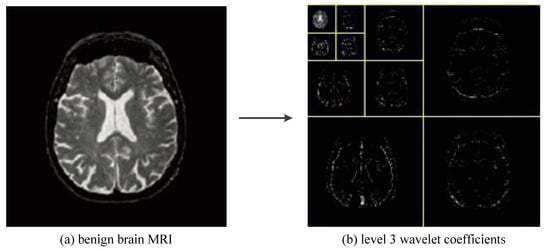

As shown in Figure 12, we greatly reduced the size of the input image by using three levels of wavelet decomposition. The approximation coefficient of level 3 is in the upper left corner of the image of the wavelet coefficient, and its size is only 16 × 16 = 256. To avoid boundary distortion, we calculate the boundary value by using the symmetric padding method [34].

Figure 12. The procedures of 3-level 2D DWT.